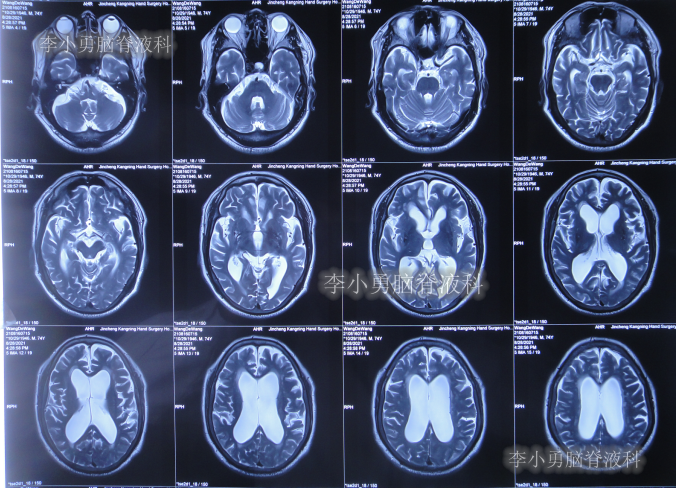

发现脑积水后8天即2020年11月6日,就诊于第2家的上海的某三甲医院,入院后再次检查(图-2)后诊断为正常压力脑积水。

图-2:2020年11月11日头部核磁